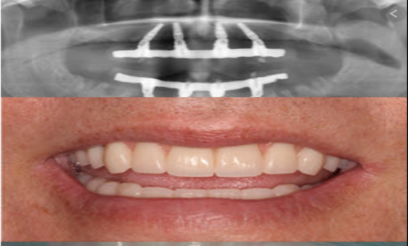

案例一:多顆種植牙手術完成後照片